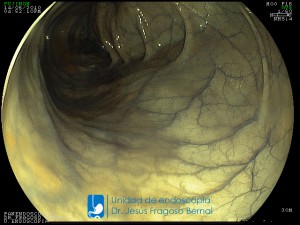

La Unidad de Endoscopía fue creada en 2002 por el Dr. Jesús Fragoso Bernal, es pionera en el estado por la utilización de la tecnología más avanzada, que nos permite ofrecer servicios integrales de diagnóstico y tratamiento para las enfermedades del aparato digestivo.